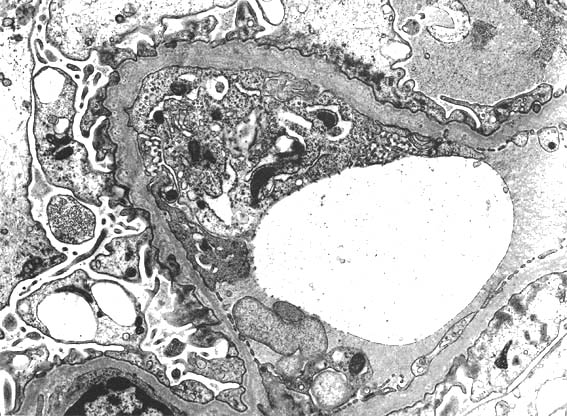

Figura 8.

Imagen de microscopía electrónica, X6.000.